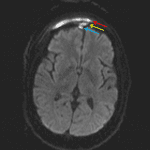

- T2/FLAIR signal hyperintensity and restricted diffusion in the right frontal sinus with peripheral enhancement

- Adjacent peripherally enhancing right frontal scalp subgaleal collection measuring 6 x 1 cm with associated restricted diffusion

- Subjacent thin epidural collection with restricted diffusion and surrounding dural thickening and enhancement

- Frontal sinusitis with epidural abscess and subgaleal abscess

Right frontal sinusitis complicated by extension through the inner and outer tables with a contiguous right frontal subgaleal abscess and small epidural abscess. Surrounding right greater than left frontal scalp and right periorbital cellulitis. Postseptal right orbital cellulitis involving the superior extraconal orbit with associated right proptosis but no discrete intraorbital abscess. No evidence of cerebritis or brain abscess.